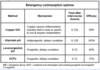

What is the most effective emergency contraceptive?

Copper intrauterine device (IUD)

contraindicated if the patient has acute cervicitis or PID; emergency contraceptive pills are less effective